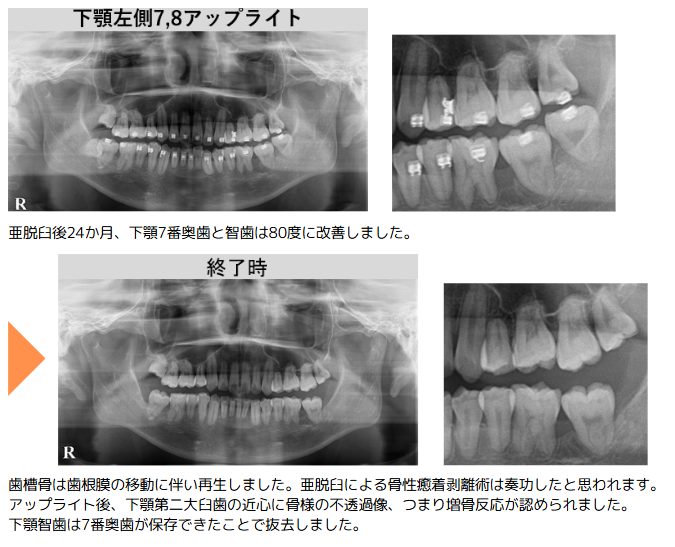

水平の下顎左側奥歯の7番に智歯が覆い被さる重積状埋伏の状態を呈していました。骨性癒着の可能性もあったため、原因が不明な症状に対し原因を仮定して治療を行い、その反応から原因を特定する方法で治療を進行。治療の途中では骨性癒着が認められたため、亜脱臼による剥離術を実施。また、喫煙習慣があることから歯周病の治療も併用し、下顎左側奥歯の7番と智歯の両方を直立させました。直立後の経過観察において、下顎左側奥歯の7番の近心に歯槽骨の増骨反応が認められたため、同部位の保存を決定しました。もし保存が困難だった場合は智歯を活用する「二の矢」を視野に入れ、診断段階から複数の治療シナリオを想定しています。

一方、智歯は下顎枝に接触し、それ以上の配列が困難と判断したため抜歯としました。なお、直立後の抜歯は埋伏時に比べて外科的侵襲が少なく、予後も良好とされます。話が前後しますが、上顎前歯部の叢生および被蓋の改善を目的とし、上顎両側4番目の歯の抜歯も併行して実施しました。

この症例では失われる可能性のあった大臼歯の保存を最優先に考えました。過去に抜歯と診断されていた下顎左側奥歯の7番を、治療的診断を用いて歯の直立・保存を目指しました。下顎左側奥歯の7番を保存できたことは、咬合の安定だけでなく、歯周病の改善にも大きく寄与します。治療方針の選択には常に様々な可能性持つことが、良好な治療結果に繋がると考えています。